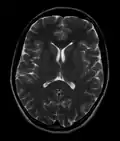

![]() Cross-sectional T1-weighted MRI of a healthy human brain acquired with an ultra high-field MR of 7 Tesla field strength | |

- T2-weighted (T2W) images: CSF is light, but fat (and thus white matter) is darker than with T1. T2-weighted images are useful for visualizing pathology.[26]